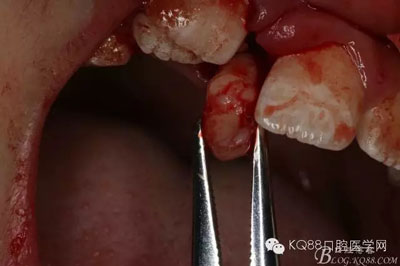

圖12.持針器取出多生牙